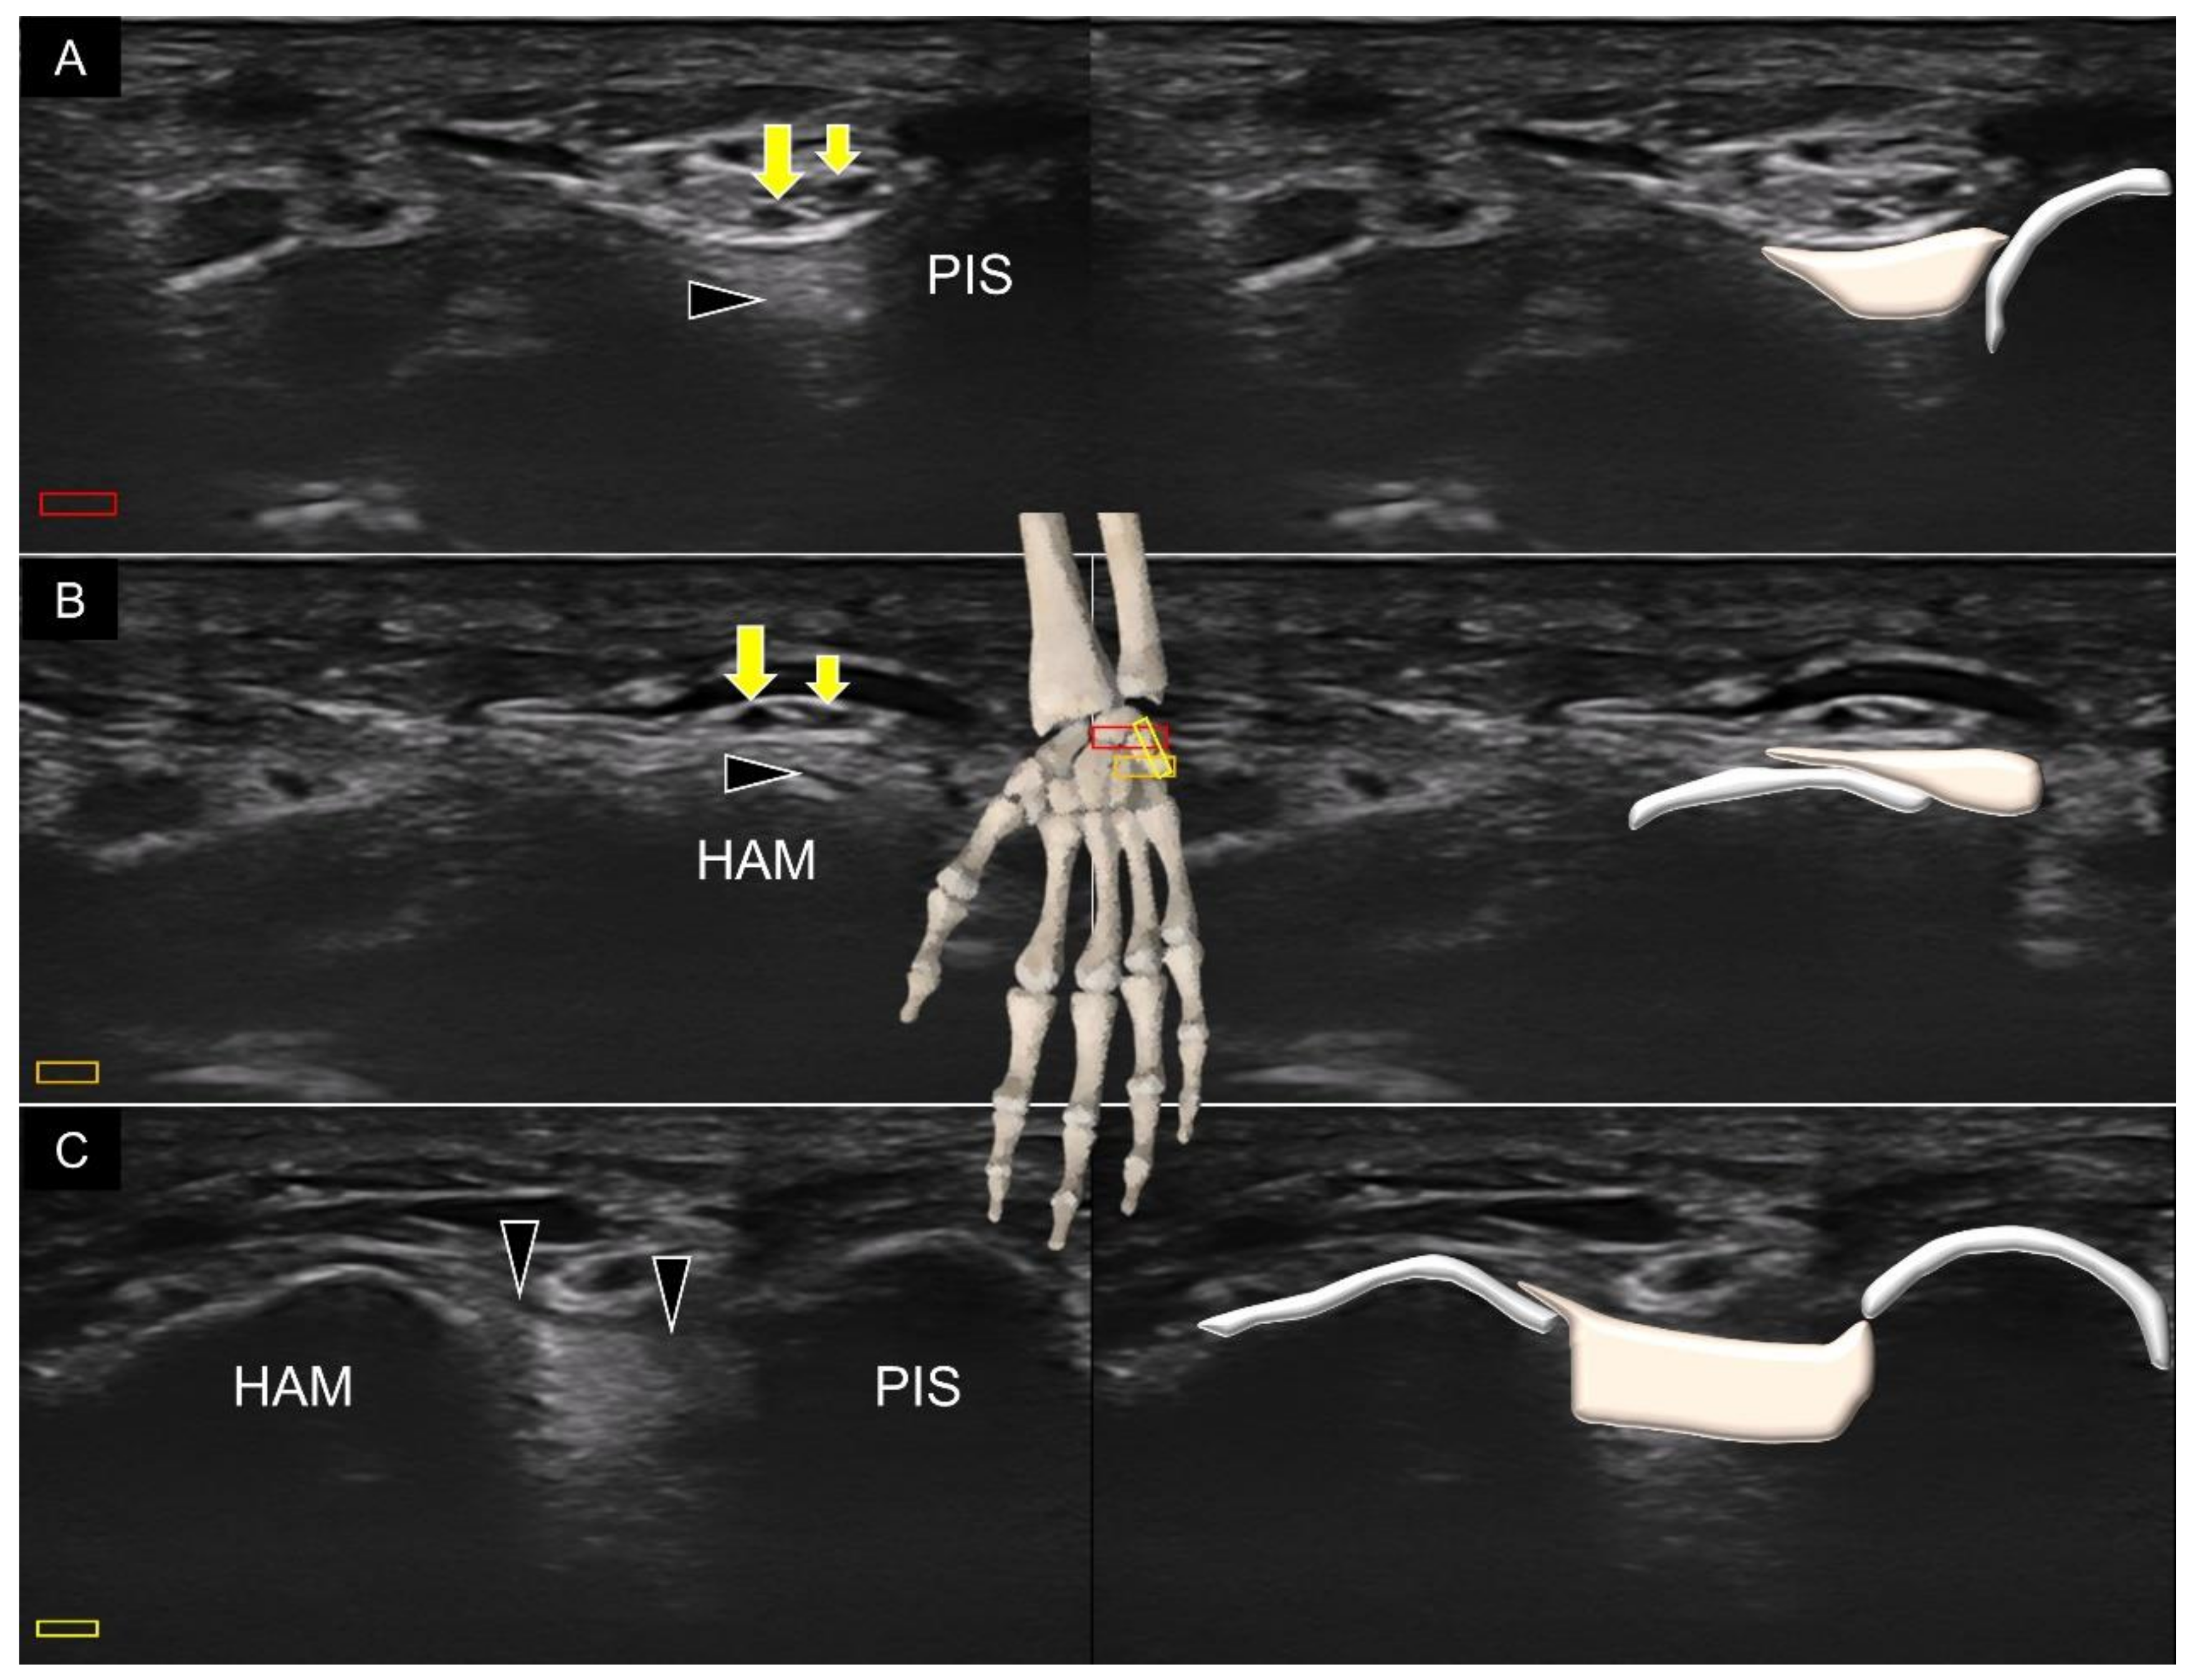

3. Sonoanatomy of Volar Extrinsic Carpal Ligaments

3.3. Attachment to the Triquetrum

4. Sonoanatomy of Volar Intrinsic Carpal Ligaments